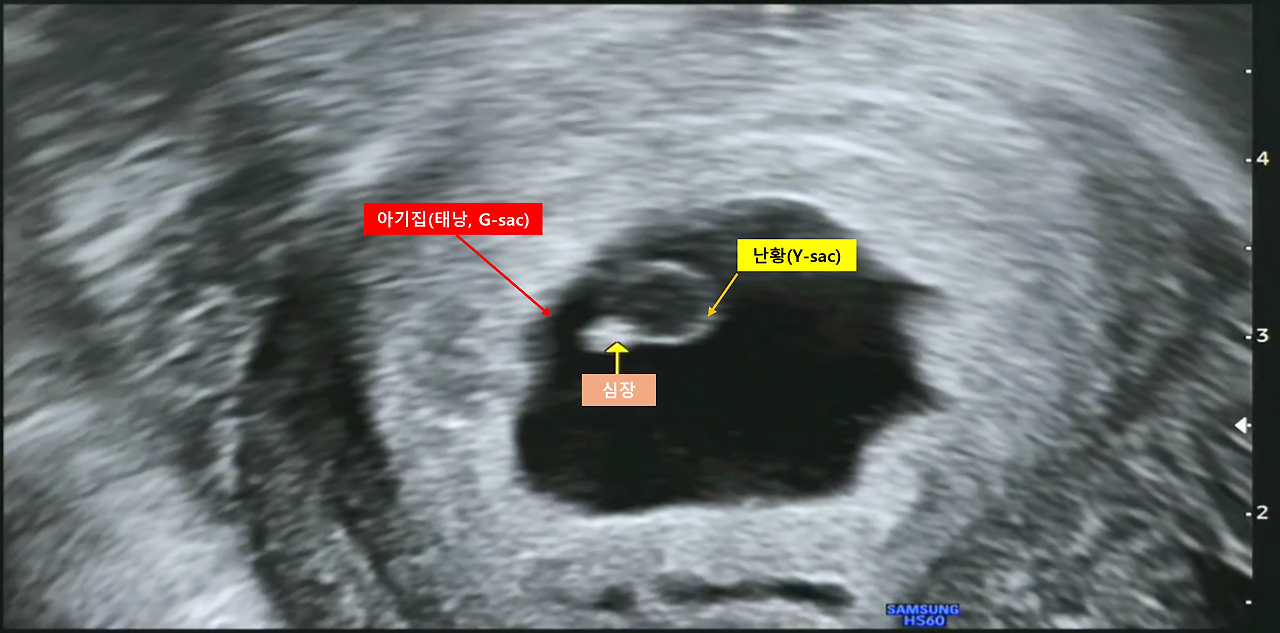

병원에서 찍은 아기집 초음파 사진을 카톡을 통해 받았습니다. 6주 0일이라고 합니다. 또 울컥하네요.

[초음파로 본 아기집]

아기집도 잘 보이고 심장 뛰는 모습도 잘 보이고, 임신 5주 차에는 '난황(Y-sac)이 보여야 할 시기'라고 하는데 난황도 잘 보입니다.

[초음파 사진 - 아기집, 난황, 심장]

참고로 난황은 보통 동그란 반지 모양(초음파 사진을 보니까 그렇네요)처럼 생겼고, 탯줄로 엄마와 연결되어 영양분을 공급받기 전까지는 이 난황을 태아가 먹고 자란다고 합니다. 전 처음부터 산모와 배아가 탯줄로 연결되어 영양분을 공급하는 줄 알았는데... 참 무식하네요. 저만 그런가요?